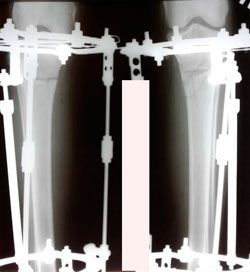

Исходник - 24 года.

Дата операции - 05.11.2020

Диагноз: Варусная деформация голеней + Ротация с обеих сторон.

на фиксации

Дата снятия аппаратов - 05.02.2021